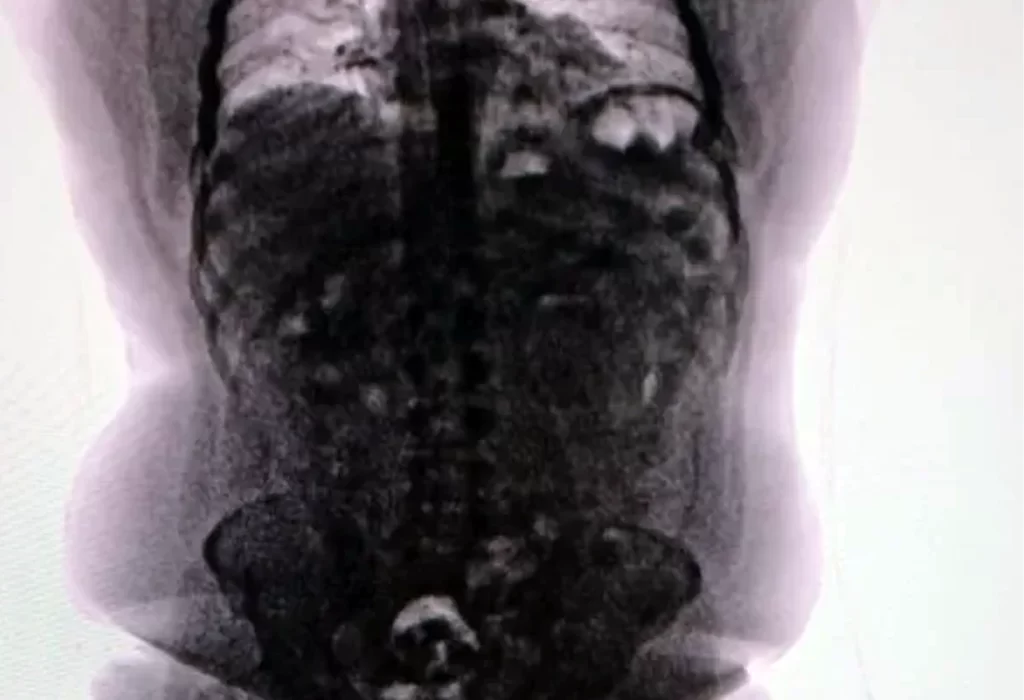

Durante el procedimiento de seguridad, agentes de la Policía de Seguridad Aeroportuaria (PSA) advirtieron señales de alerta: el sospechoso mostró un comportamiento inusualmente nervioso, contaba con un pasaporte recientemente emitido y presentaba un trayecto aéreo fuera de lo común. Estas observaciones llevaron a realizarle un escaneo corporal, que confirmó la presencia de objetos extraños en su abdomen.

Tras el hallazgo, fue derivado al Hospital de Ezeiza, donde durante cuatro días evacuó 90 cápsulas que contenían 698 gramos de cocaína. Todo el proceso estuvo bajo estricta supervisión médica y custodia policial.